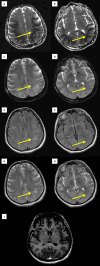

We report the case of a 35-year-old female patient who presented to a tertiary referral hospital in a persistent vegetative state (PVS) following a cardiac arrest that occurred approximately one hour after an elective cesarean delivery for a postterm pregnancy complicated by preeclampsia. Magnetic resonance imaging (MRI) of the brain performed seven days after the cardiac arrest showed findings consistent with posterior reversible encephalopathy syndrome (PRES). Following transfer to our hospital, the patient was carefully evaluated, stabilized, and successfully weaned off mechanical ventilation. However, due to the lack of neurological recovery, the decision was made to transfer her to a neurorehabilitation center for further management. This case report explores the potential link between PRES and PVS.